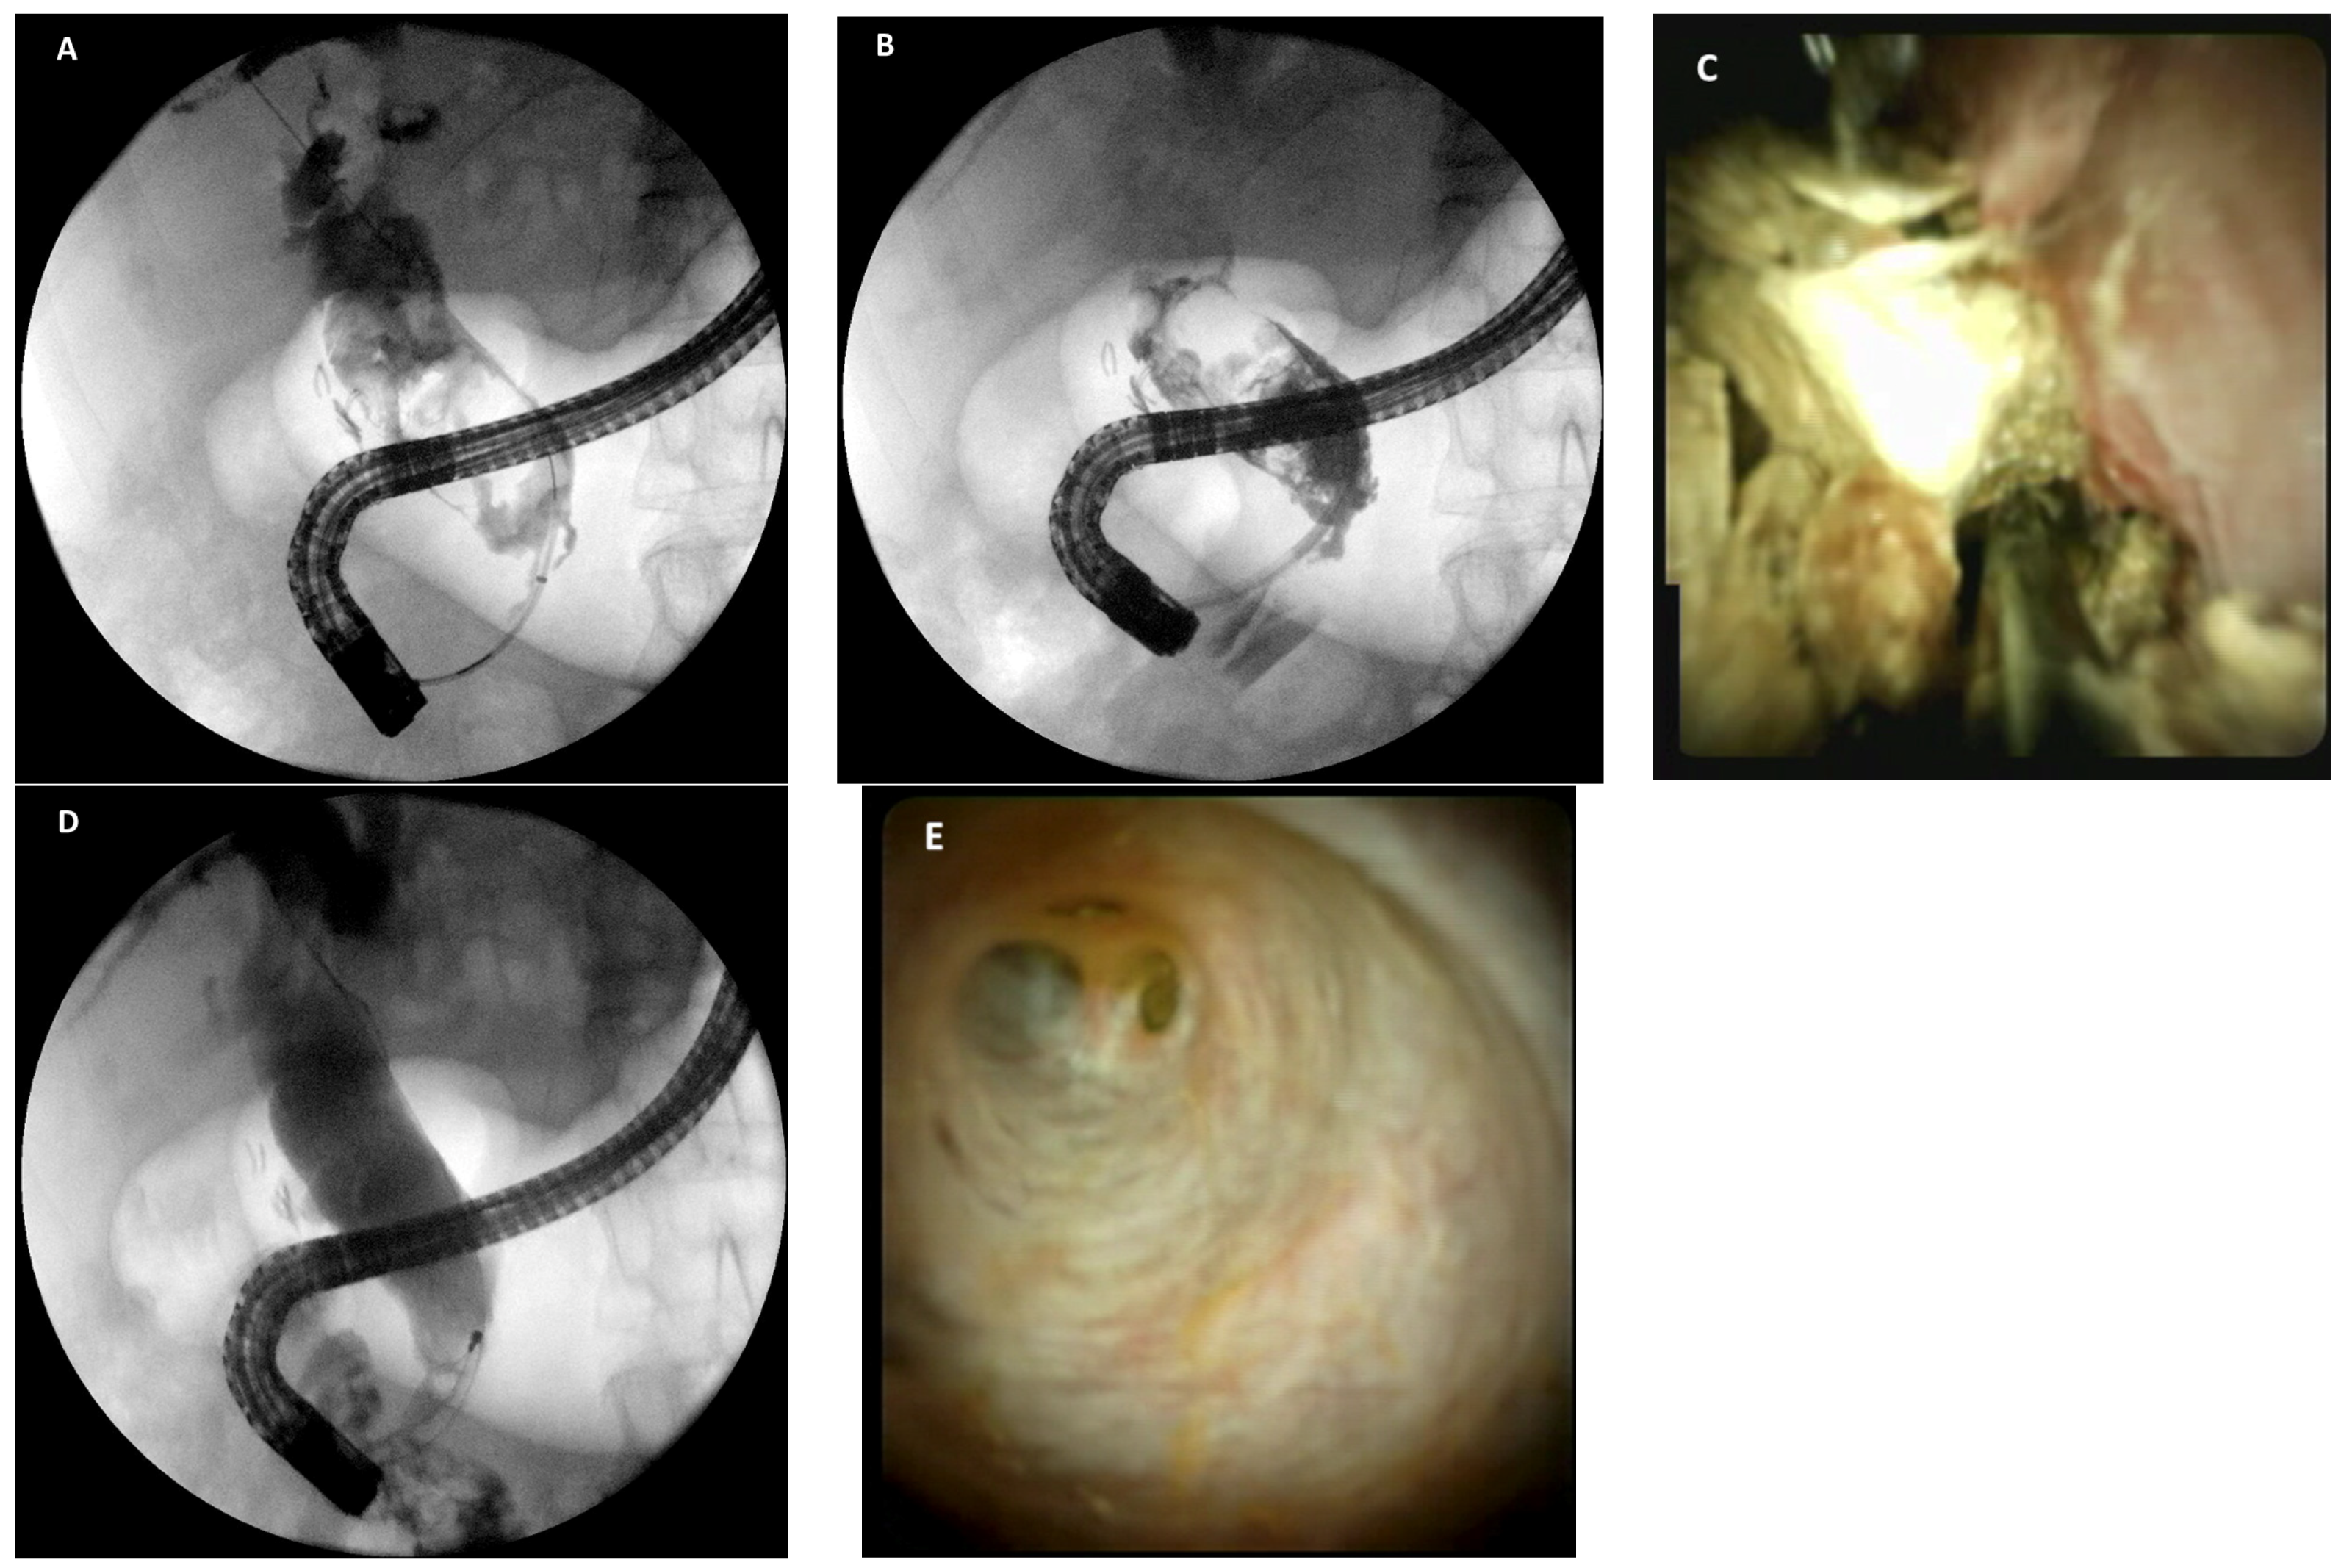

- Bhandari, S.; Bathini, R.; Sharma, A.; Maydeo, A. Usefulness of single-operator cholangioscopy-guided laser lithotripsy in patients with Mirizzi syndrome and cystic duct stones: Experience at a tertiary care center. Gastrointest. Endosc. 2016, 84, 56–61. [Google Scholar] [CrossRef] [PubMed]

- Chon, H.K.; Park, C.; Kim, T.H. Minimally Invasive Approach Using Digital Single-Operator Peroral Cholangioscopy-Guided Electrohydraulic Lithotripsy and Endoscopic Nasogallbladder Drainage for the Management of HighGrade Mirizzi Syndrome. Clin. Endosc. 2021, 54, 930–934. [Google Scholar] [CrossRef]

- Binmoeller, K.F.; Thonke, F.; Soehendra, N. Endoscopic treatment of Mirizzi’s syndrome. Gastrointest. Endosc. 1993, 39, 532–536. [Google Scholar] [CrossRef]